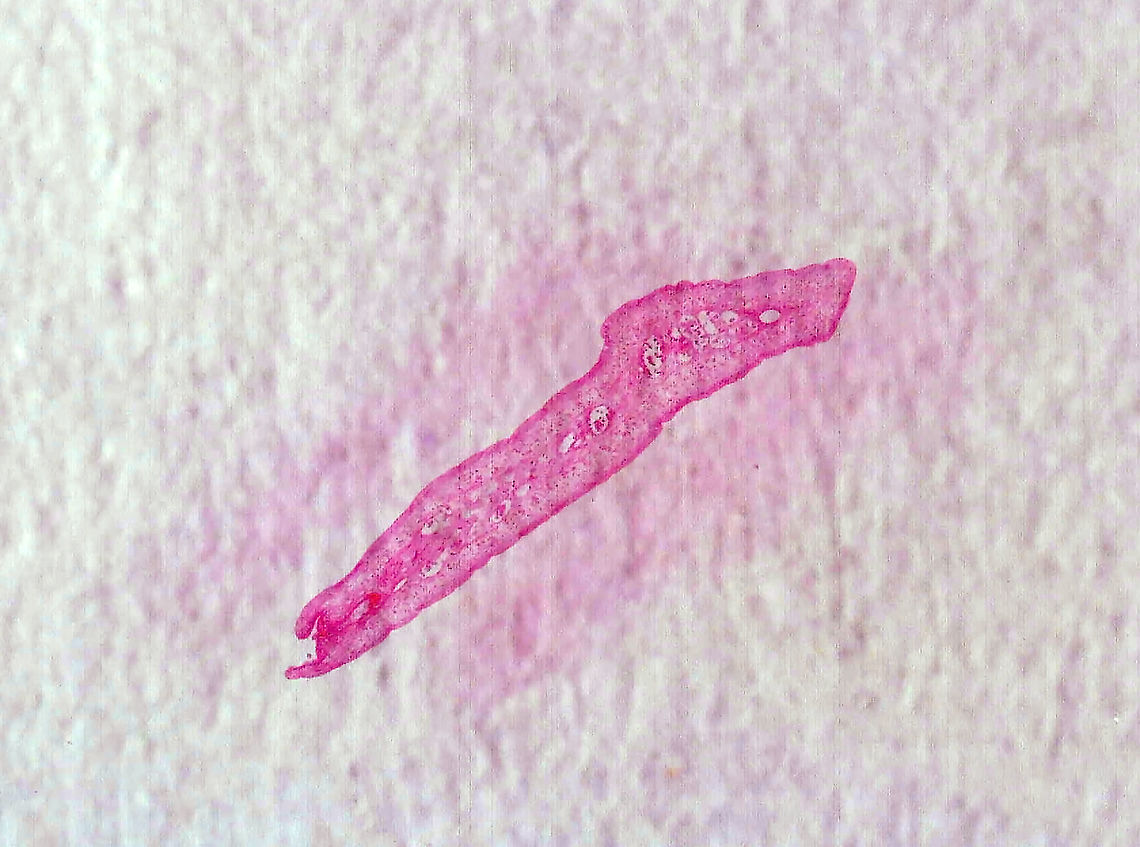

Beef Tapeworm - Taenia saginata

*Cross-section microscope slide

''Taenia saginata'', commonly known as the beef tapeworm, is a zoonotic tapeworm belonging to the order Cyclophyllidea and genus ''Taenia''. It is an intestinal parasite in humans causing taeniasis and cysticercosis in cattle. Cattle are the intermediate hosts, where larval development occurs, while humans are definitive hosts harbouring the adult worms.